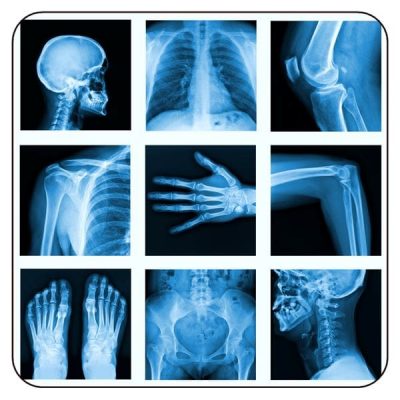

Most NPs have a basic understanding of x-ray interpretation, but many question the “why and how” of radiology, especially with more complicated patient films. This two-part session takes the participant from a basic understanding of the shades of black and white on an x-ray film to the ability to identify pneumonia, CHF, cardiomegaly, bowel obstruction, spine injuries, Salter Harris fractures, and much more. Within 2 ½ hours, it’s from novice to expert with radiology.

Sample